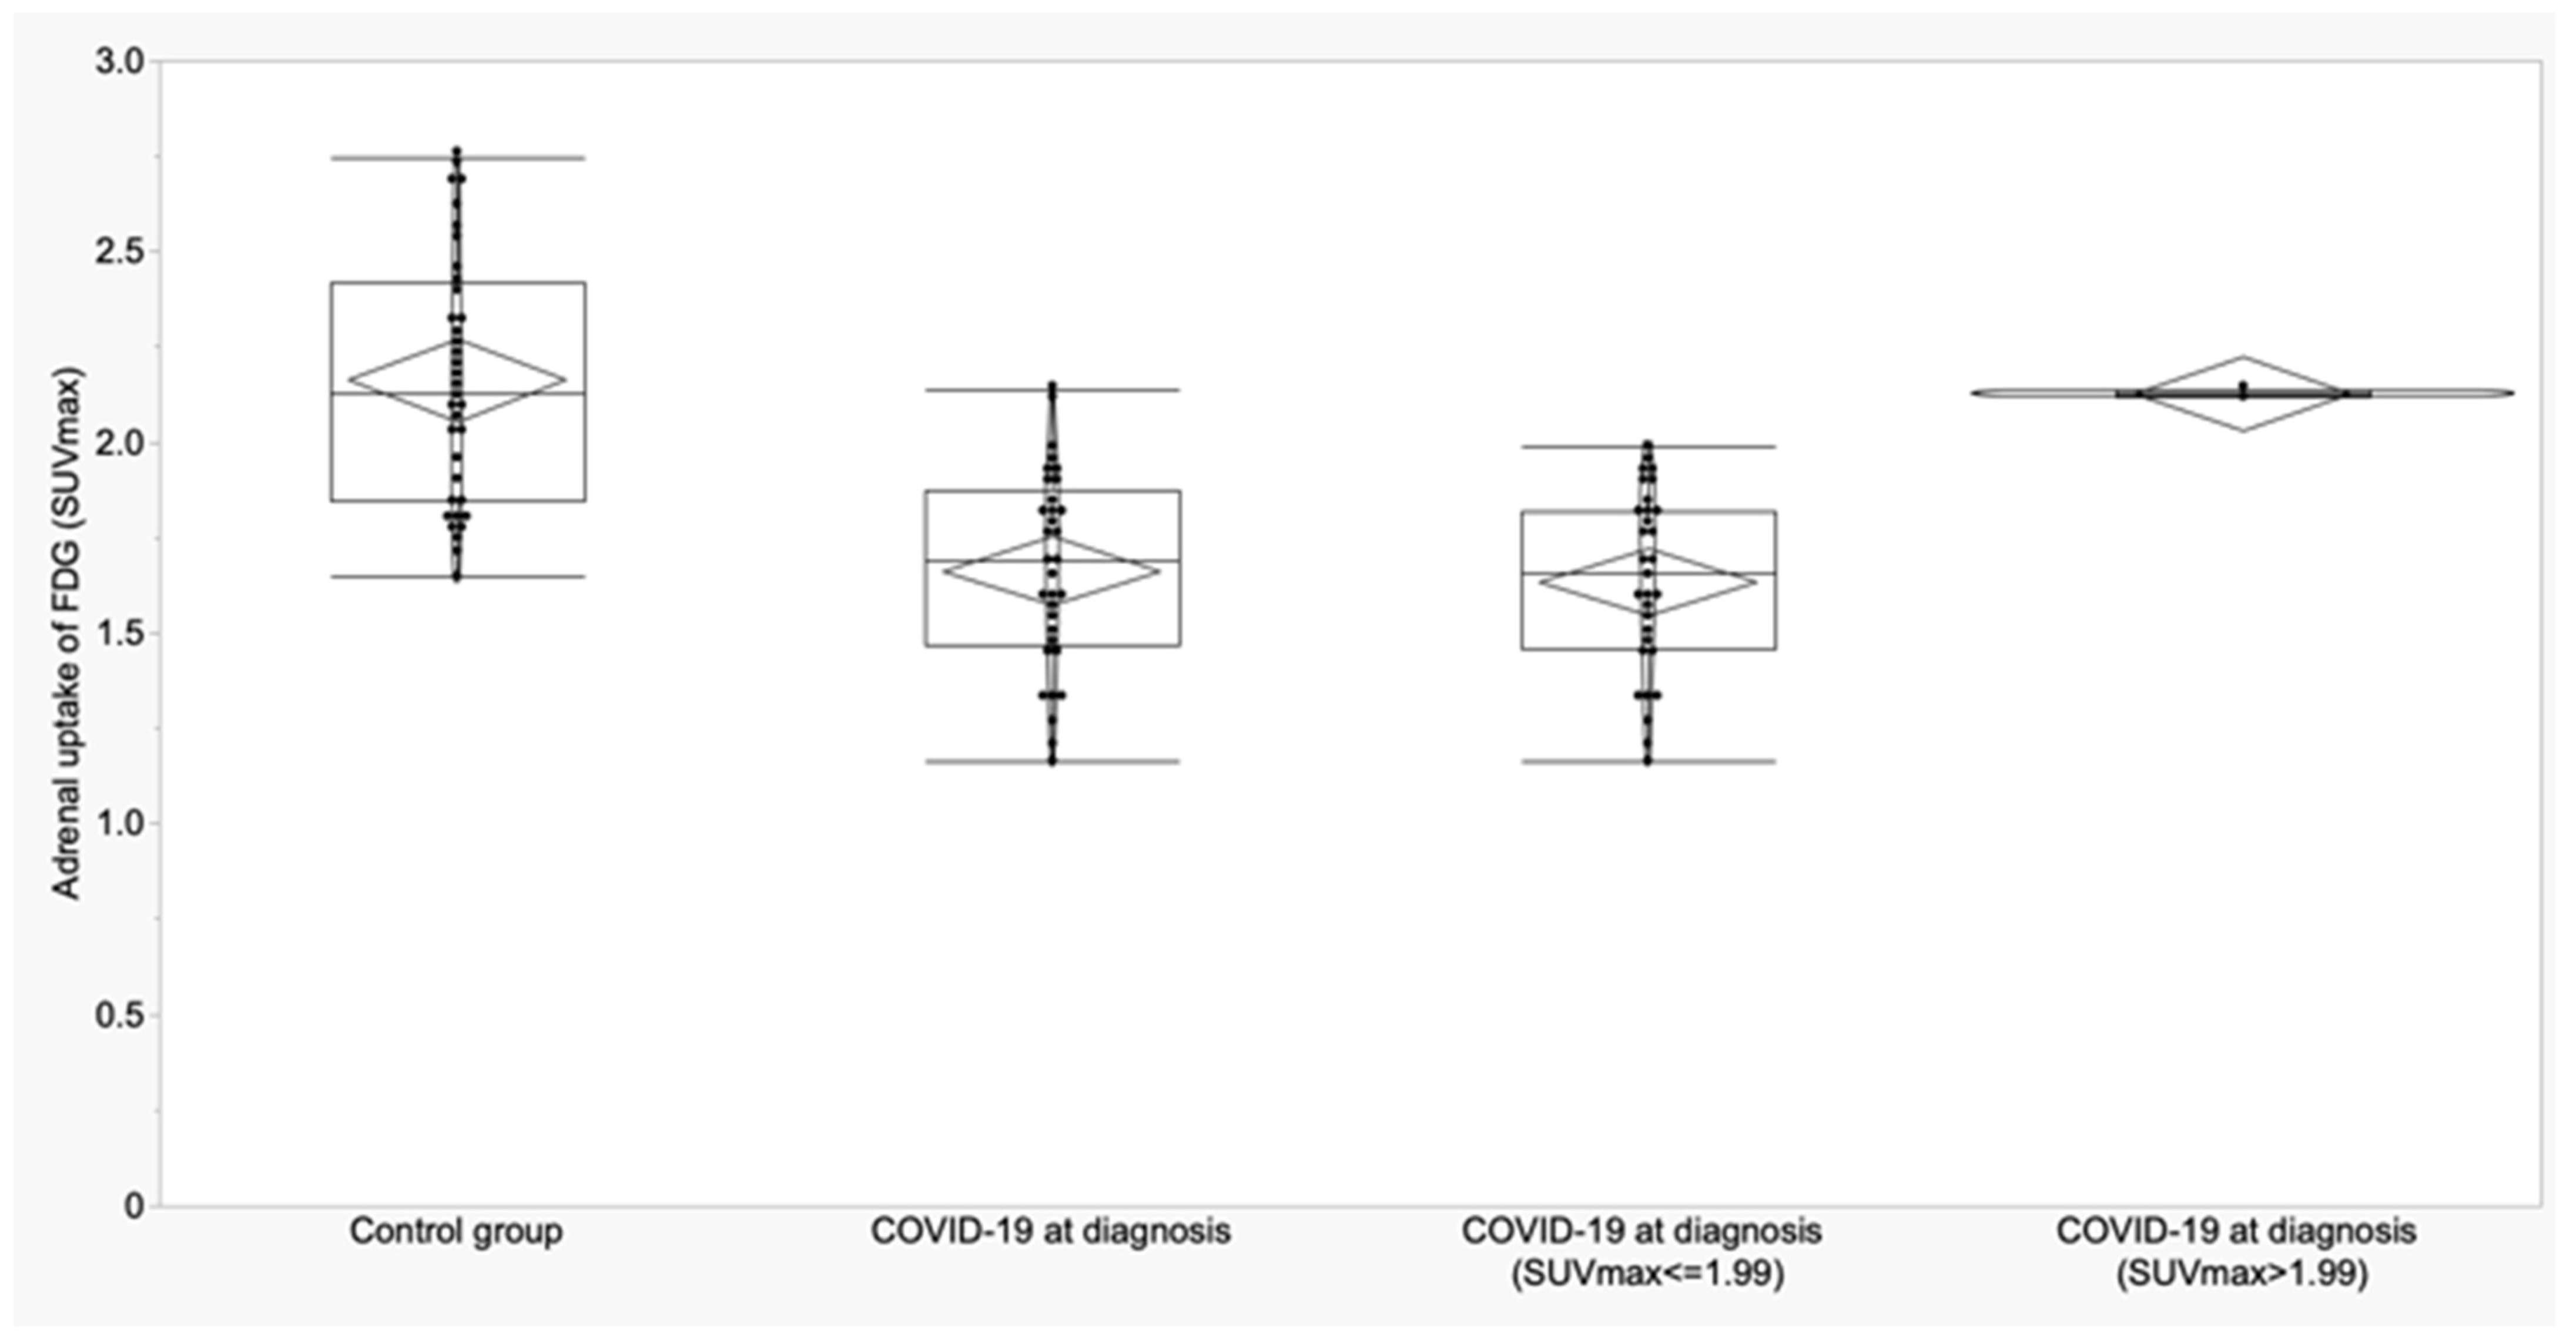

3.2. Thyroid and Adrenal Gland Analysis

| Adrenal (SUVmax) | 2.16 ± 0.32 (2.05 to 2.27) | 1.65 ± 0.26 (1.55 to 1.75) | 1.73 ± 0.26 (1.40 to 2.06) | <0.0001 | <0.0001 | 0.003 | 0.58 |